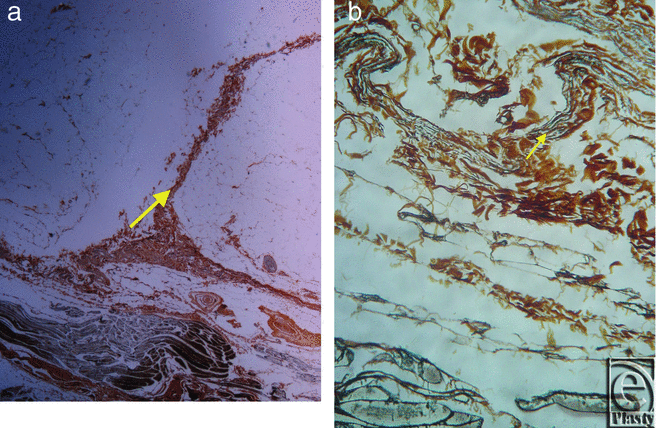

![]() |

| Figure 5. Inframammary crease. (a) Reticulin stain ×25. (b) Reticulin stain ×200. The collagen type III fibers are stained in black and radiate from the underlying muscle fascia. |